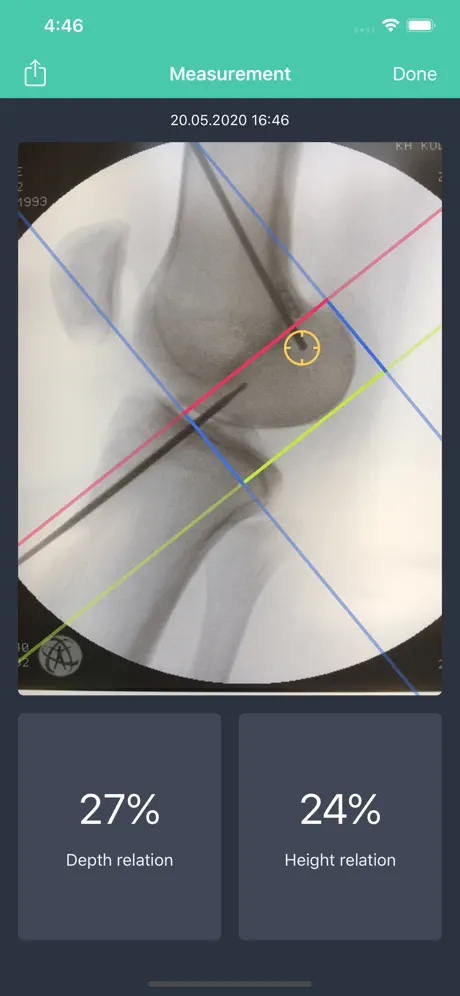

The app will display the relative ratio of your target point in reference to the outlines of the bone of the femoral condyles. The measurement values relate to the relative distance of the target point of the most posterior and proximal border of the condyles.

This app will display the relative distance (in percent) of the entry point of the guide wire into the joint in relation to the total anterior posterior (AP) distance of the proximal tibia (100 %).

The app will display the relative ratio of your target point in reference to the outlines of the bone of the femoral condyles. The measurement values relate to the relative distance of the target point of the most posterior and proximal border of the condyles.

This app will display the relative distance (in percent) of the entry point of the guide wire into the joint in relation to the total anterior posterior (AP) distance of the proximal tibia (100 %).